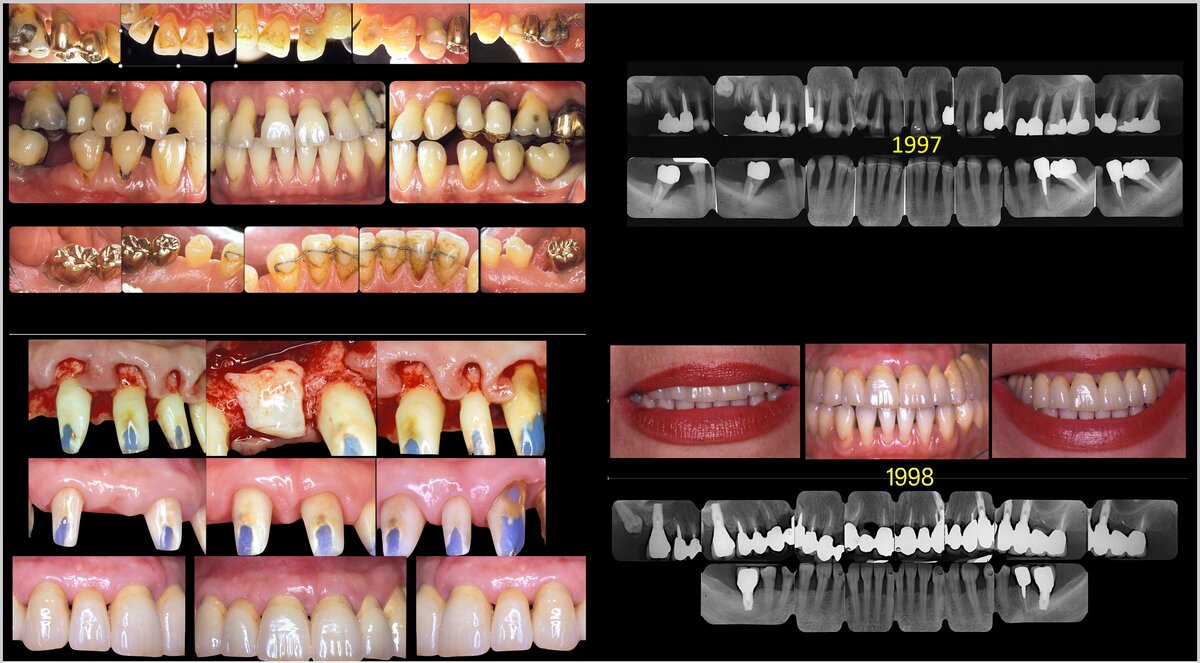

If the goal is to realize a prosthesis with optimal aesthetics, we should first define what we mean by “optimal aesthetics” because the aesthetic perception varies widely from country to country, from person to person, and also between patients and dentists (Tonetti et al, 2025). If we define optimal aesthetics as a smile that appears naturally beautiful and in harmony with the patient’s facial features—so that one should not perceive the difference between restored and natural teeth—we find that this task is extremely difficult to accomplish in patients who have lost five or more teeth and 70-80% of the remaining tooth support (Figure 1). Unfortunately, the only way to achieve “optimal aesthetics” is often to replace the lost tissues with artificial gums. But can this kind of aesthetics be defined as “optimal”?

The consequences of this approach, from both aesthetic and functional perspectives, are substantial. If the goals of periodontal therapy have been achieved (Sanz et al, 2020; Tomasi et al, 2022), the teeth can be orthodontically moved and intruded to compensate for the soft- and hard-tissue loss, and a natural-looking smile is easier to regain (Figure 3). From a functional point of view, the benefit of keeping virgin, and not crowned, teeth is even greater. In teeth that have lost more than 50 per cent of attachment, in order to avoid “black triangles” between the teeth, the prosthetic finishing margin must be located not at the cementoenamel junction but at the gingival margin level, i.e. at the apical third of the root.